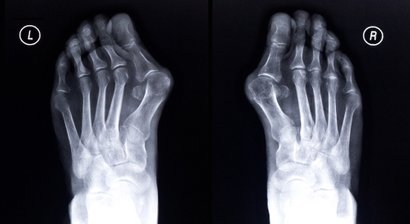

Fußoperationen

Unter Fußschäden leiden rund 60 Prozent der Erwachsenen in unseren Breiten. Die meisten Fußfehlstellungen können mit einer nicht-invasiven Therapie, also mit Einlagen, Bandagen oder orthopädischen Spezialanfertigungen behandelt werden.  Meine Praxis steht einmal in der Woche ganz im Zeichen des...